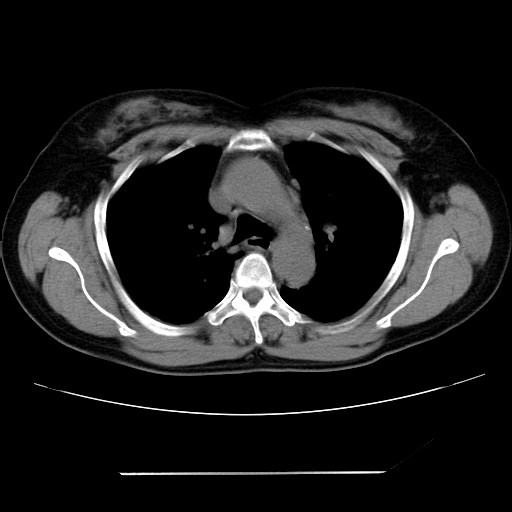

标题: CT24018:女性,62岁,咳嗽4年,无热,胸部CT扫 [打印本页]

女性,62岁,长期咳嗽,既往从事工作有粉尘接触,有高血压病史,110/150mmhg,近日咳嗽加重,脸面浮肿,请大家帮看下,

1、尘肺;2、慢性支气管炎合并肺部感染;3、心影增大(左房、左室大),考虑高血压性心脏病。

慢支并肺部炎症;右肺结核球?主肺动脉、右肺动脉影不宽,右心室不大,不支持肺心病;无心包积液。

1)慢性支气管炎并肺部感染、肺气肿。2)肺间质纤维化。